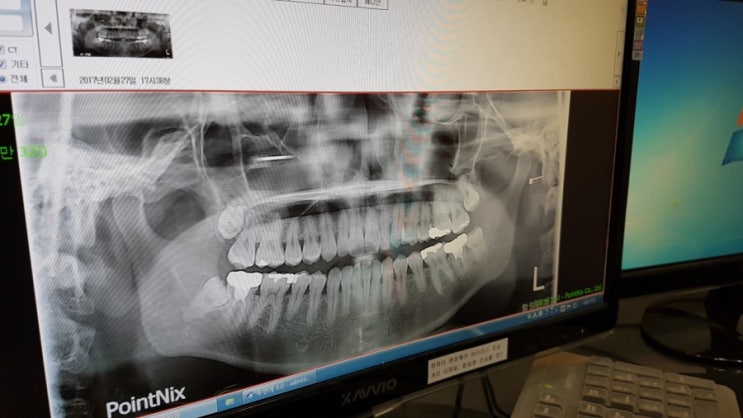

사랑니.... 나를 미추어버리게함ㅜㅜ

일주일 넘게 지소닐 미취게하는 사랑니.. 더이상 무섭다고 미룰수없어서 진짜큰맘먹고 속전속결 치과를 찾...